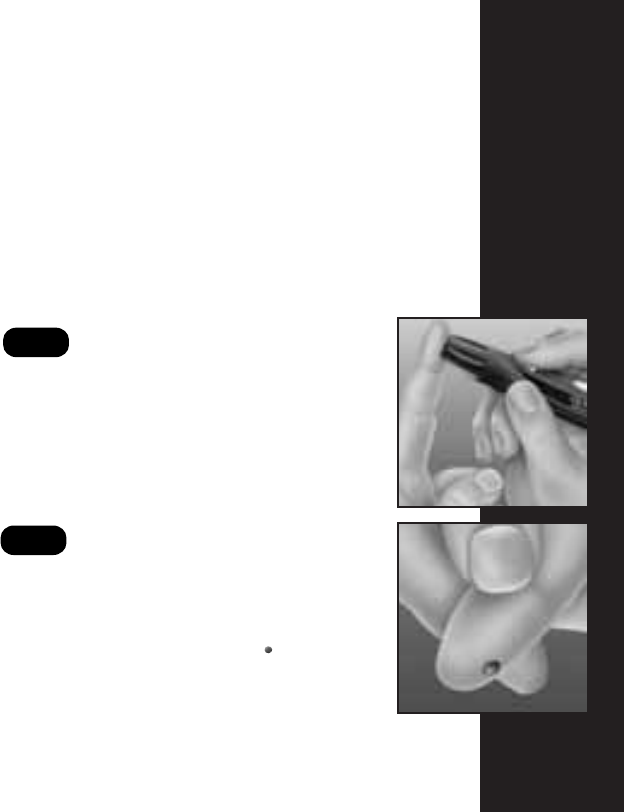

Le fait de masser doucement le bout du doigt

vous aidera à obtenir une goutte de sang bien

ronde. Ne pressez pas trop le site de ponction.

Massez le bout du doigt.

Positionnez le dispositif.

Tenez fermement le dispositif OneTouch

®

UltraSoft

MC

contre le côté de votre doigt.

Appuyez sur la gâchette.